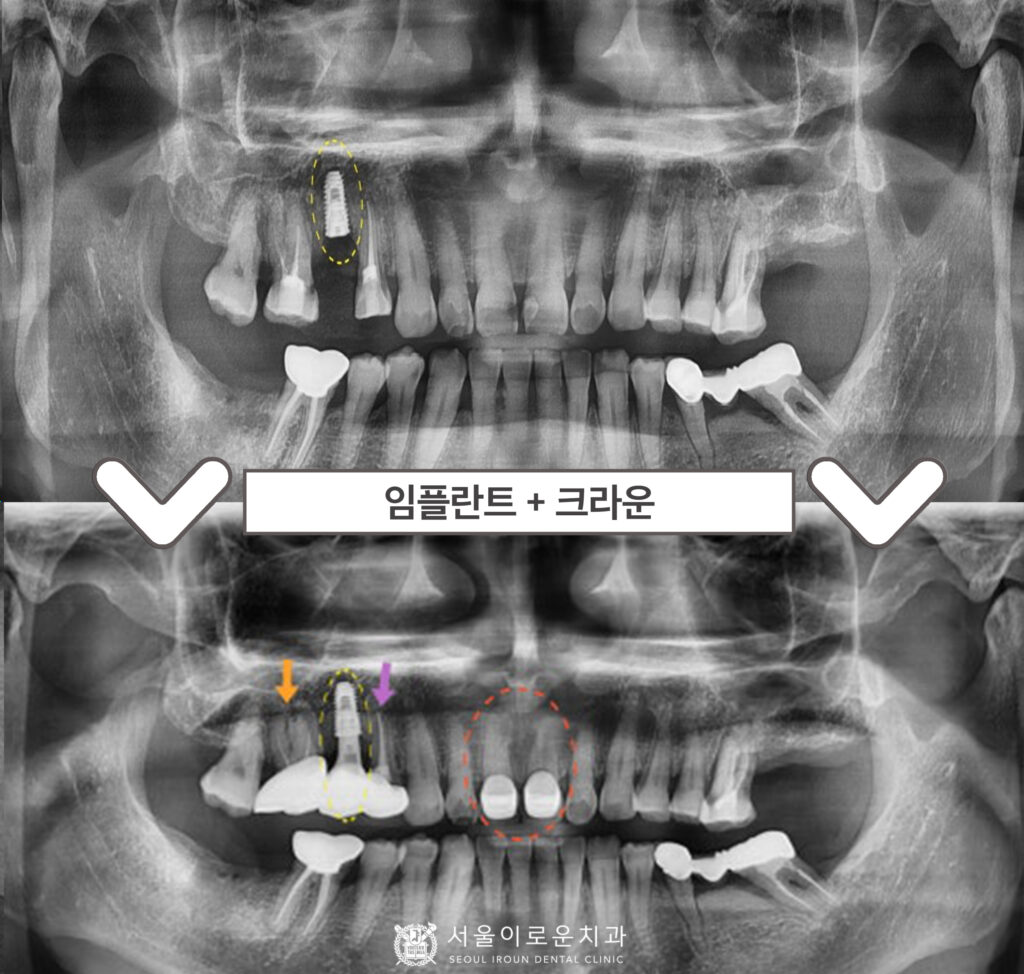

노란색 동그라미의

오른쪽 위턱 두 번째 작은 어금니(#15)의

뿌리 주변으로 잇몸뼈가

많이 흡수되어 있었으며,

충치도 심한 것을 확인할 수 있었습니다.

이 경우 살려 쓰기 어려울 것으로 판단되어

안타깝지만 발치가 필요한

상황이었습니다.

그리고 보라색 화살표의

오른쪽 위턱 첫 번째 작은 어금니(#14) 또한

통.증을 호소하셨는데요.

충치가 치아의 허리 부분에 해당하는

치경부 깊이 진행되어 있어

신경치료 후 크라운 치료가 필요하였습니다.

또한 주황색 화살표의

오른쪽 위턱 첫 번째 큰 어금니(#16)는

예전에 신경치료까지만 진행이 되어있고

크라운 수복을 하지 않은 상태였는데요.

그렇다 보니 레진 경계부에

이차우식이 진행되어

크라운 치료가 필요하였습니다.

그리고 마지막으로

환.자분께서 말씀하셨던

빨간색 동그라미의 앞니(#11,12)

충치 부분은

그냥 육안으로 보기에도

두 개의 치아 사이에

까맣게 충치가 생긴 것을

확인할 수 있었는데요.

다행히 충치가 신경까지

진행이 되지 않은 상태라

신경치료는 하지 않아도 되는 상황이었지만

충치가 있는 치아머리 일부를 삭제하고 나면

잔존 치질량이 얼마 되지 않아

치아가 약해지기 때문에

충치 제거 후 레진으로 보강한 뒤

크라운 치료를 계획하였습니다.

오른쪽 위턱 두 번째 작은 어금니(#15)는

발치 후 염증조직을 깨끗하게 제거하고

소독한 후에 뼈이식을 동반한

임플란트 즉시 식립을 도와드렸는데요.